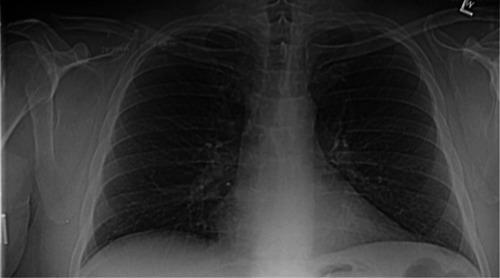

Clavicular eosinophilic granuloma causing adult shoulder pain.

Rare Tumors. 2013 Mar 1;5(1):e8. doi: 10.4081/rt.2013.e8. Print 2013 Feb 11.